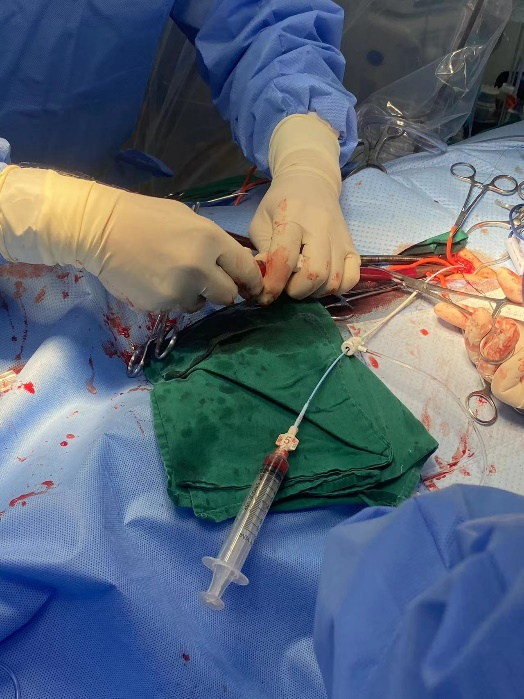

体外循环是及时有效的抢救手段

手术方案分析:患者为功能型二叶瓣,右无冠窦可见融合,重度钙化1191积分,超声提示主动脉瓣重度狭窄重度返流,左冠高度约10.0mm,左冠瓣叶长,左冠闭塞风险高,术中球囊预扩张行风险评估,根据预扩情况判断是否需要左冠保护。患者双侧髂动脉-股动脉走形稍迂曲,管腔未见明显狭窄,推荐右侧股动脉做为主入路。此外,因患者术前存在严重心衰症状,血压低,LVEF值仅31%,需大剂量血管活性药物维持,TAVR术中循环崩溃风险高,遂决定在体外循环辅助并行循环下操作,使用Venus-Plus二代可回收输送系统,以增强手术安全性。

左侧腹股沟区2cm微小切口进行股动静脉插管建立外周体外循环后并行循环。

手术方案分析:患者为TYPE 1型二叶瓣,左右融合,左冠高度约9.7mm,右冠高度约15.4mm,左冠瓣叶超过冠脉开口上缘,初判左冠闭塞风险较高,拟术中球囊预扩张行风险评估,根据预扩情况判断是否需要左冠保护。术前CT提示主动脉弓呈锐角并钙化,植入器过弓风险高,综合决定首选启明Venus瓣膜L26,22mm球囊预扩,使用有良好过弓性能的启明Venus-A pro三代输送系统,可回收的同时改善过弓难度以及同轴性。患者循环不稳,进行左侧腹股沟区切开,游离股动静脉缝好荷包备用,随时根据需要进行体外循环保护,保障病人安全。

外科TAVR团队在应对高危及循环不稳情况时具有显著优势,拥有的处理手段最多,反应速度最快,处理特殊情况最及时,为患者提供最佳安全保障。

在开展这两台手术前,刘健教授团队充分评估患者情况及各项评估数据,制定了详细的冠脉保护及瓣膜植入方案,团队表示:“发生循环崩溃对病人来说是非常危险的,因此一定要做好例如体外循环甚至开胸抢救等一系列的预案,才是对患者安全的最大保障”。

在术中成员紧密配合下,最后通过扎实的操作基础顺利植入瓣膜,释放位置良好;第一位患者体外循环调增内环境后即刻撤离,术后复查各项指标正常,患者症状得到有效改善。第二位患者体外循环备用,为TAVR顺利完成提供安全保障。两台手术的顺利开展,体现了团队应对高危重症及复杂病例的国内领先技术水平。未来,团队必将孜孜以求,不断突破,为大湾区乃至全国患者提供更加优质的医疗服务。